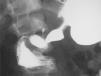

La analítica solo muestra elevación moderada de amilasa 292 U/l (19-161 U/l). Se realiza tránsito intestinal con contraste en el que se observa obstrucción a la salida del estómago con acortamiento antral y defecto de llenado de la segunda porción duodenal (fig. 1). La laparotomía confirma la invaginación gastroduodenal (fig. 2) y la presencia de dos pólipos sésiles de 3 x 5cm y 4 x 2cm, realizándose una desinvaginación manual y gastrostomía antral con exéresis de las lesiones polipoideas. El estudio anatomopatológico es compatible con pólipos de tipo hamartomatoso. La recuperación del paciente es satisfactoria y a lo largo de su seguimiento se han observado numerosos pólipos en el estómago, el duodeno, el colon y el sigma, sin que haya presentado nuevas complicaciones.